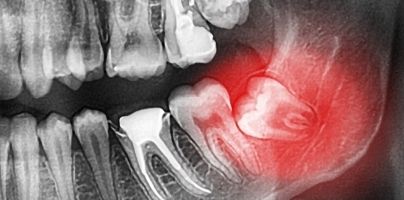

Wisdom

If you are worried about or having problems with your wisdom teeth then book in to see us for a wisdom tooth assessment. We offer a student discount of 10%.

OPG

An OPG (Orthopantomagram) is a panoramic scanning dental X-ray of the upper and lower jaw. It is also sometimes called Orthopantomagraph or by the proprietary name Panorex. It shows a flattened two-dimensional view of a half-circle from ear to ear.